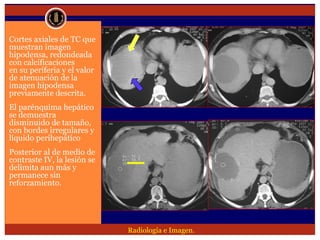

El documento presenta 6 casos clínicos de lesiones focales hepáticas evaluadas mediante tomografía computarizada multiphásica. Se describen los hallazgos radiológicos de cada caso y el diagnóstico correspondiente, incluyendo quiste hepático, hemangioma hepático, hiperplasia nodular focal, quiste hidatídico y absceso hepático. El documento provee detalles sobre el protocolo de TC multiphásica para evaluar lesiones hepáticas y características clínicas e imágenes de diferentes patologías.